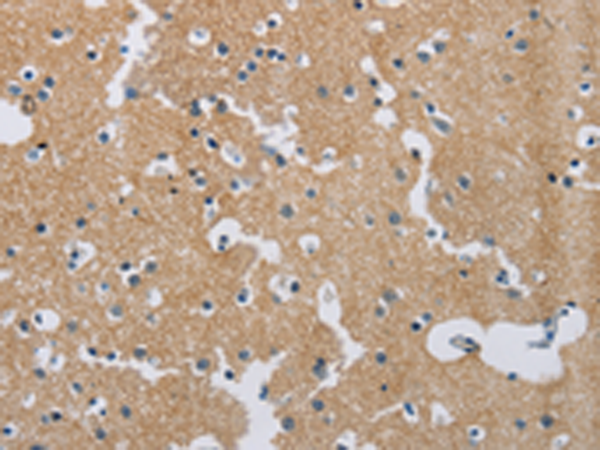

分类: 科研抗体货号: P11853别名: SYNII; SYNIIa; SYNIIb应用: WB,IHC反应种属: Human, Mouse, Rat